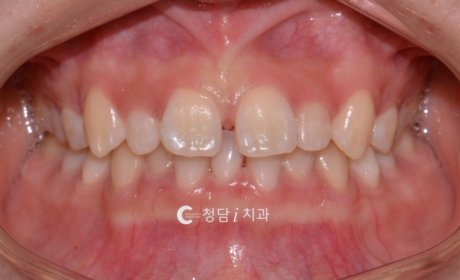

고르지 않은 치열 발치 후 교정 사례

의정부 치아교정치과 청담i치과에서는 치열이 고르지 않고 덧니와 겹침이 심한 경우, 정밀 진단을 통해 발치 교정을 진행하고 있습니다. 다음 사례는 배열이 삐뚤빼뚤해 웃을 때 치아가 고르게 보이지 않던 환자분의 교정 전후 변화입니다. 교정 전에는 치아가 겹쳐 배열되어 스마일 라인이 고르지 않고, 웃을 때 치열이 복잡해 보이는 인상이었습니다. 공간 부족으로 인해 칫솔질이 어려워 구강 관리에도 불편함을 느끼고 […]